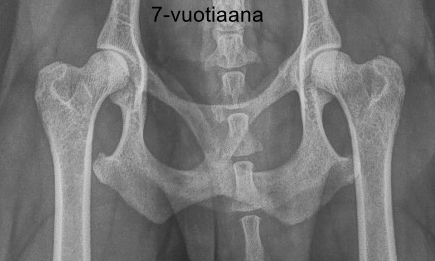

Lonkkanivelet C/B (C:lle ei lausunnossa selitystä – eikä onneksi myöskään mainintaa nivelrikosta. Lisätietoja kysyttäessä C:n syynä oli matala lonkkamalja sekä reisiluun kaulassa erottuva muutos. B:n taas aiheutti maljan yläreunan ”irvistäminen”.)

1. kontrollikuvaus 5-vuotiaana ja 2. kontrollikuvaus 7-vuotiaana

Kuvautin Entsyymin nivelet uudestaan hammaskivenpoiston yhteydessä. Kuvien välissä on kulunut neljä vuotta. Uudet kuvat näyttivät aika lailla samoilta kuin aikaisemmat, joten muutokset eivät ole edenneet nivelrikoksi. Päivitys: uusi kontrollikuvaus 7 v 10 kk iässä, samalta näyttää edelleen.